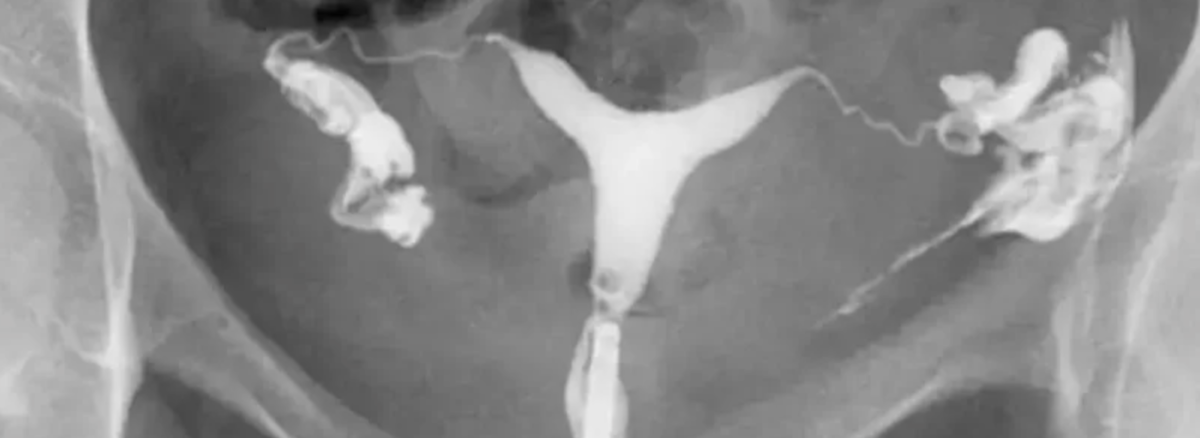

هیستروسالپنگوگرافی (Hysterosalpingography – HSG) یک روش تصویربرداری تخصصی است که با استفاده از اشعه ایکس و تزریق ماده حاجب به داخل رحم، وضعیت حفرهی رحمی و باز بودن لولههای فالوپ را بررسی میکند. این روش یکی از مهمترین آزمونهای تشخیصی در ارزیابی اولیه ناباروری زنان محسوب میشود، زیرا بسیاری از موارد ناباروری به دلیل انسداد لولههای فالوپ رخ میدهد.

در این روش، پس از تزریق ماده حاجب، تصاویر متعددی از رحم و لولهها گرفته میشود و پزشک میتواند شکل غیرطبیعی رحم، پولیپ، فیبروم، چسبندگی، سپتوم و مشکلات ساختاری دیگر را شناسایی کند.

ماده حاجب بهآرامی وارد رحم شده و سپس مسیر آن از داخل رحم به سمت لولههای فالوپ قابل مشاهده میشود.

رادیولوژیست تصاویر مختلفی را از زوایا و مراحل گوناگون عبور ماده حاجب تهیه میکند.